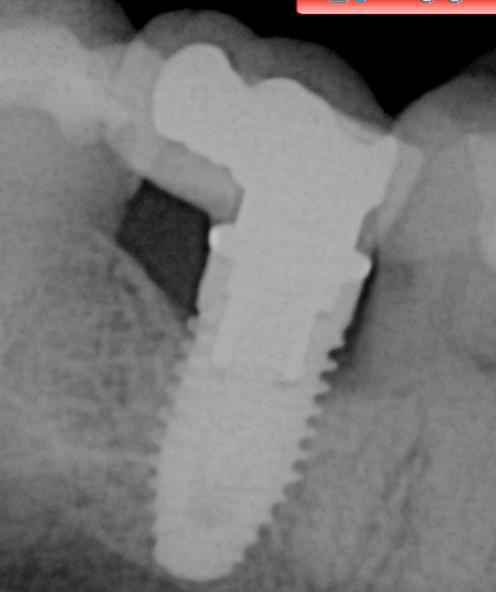

Bon patiente avec un implant un peu infecté et couronne mobile. Si vous pouviez m'aider à connaitre la marque?

J'espère que la radio vous suffit?

Nobel replace

http://whatimplantisthat.com/implant/replace-select/